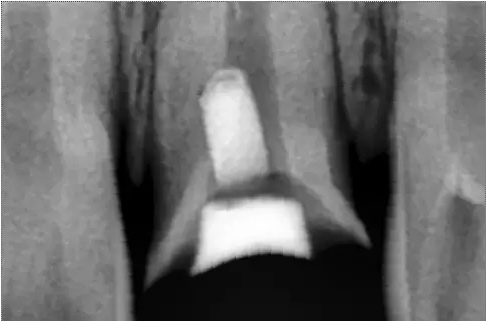

MTA修補(bǔ)后的X片

根尖區(qū)和根管中下l/3穿孔,在鏡下可用MTA根充根尖區(qū)并同時(shí)堵塞穿孔部位。根管中上部穿孔,可進(jìn)行根尖部的垂直加壓法根充.穿孔部位MTA修補(bǔ),或穿孔部位以下及穿孔區(qū)全部用MTA充填和修補(bǔ)。